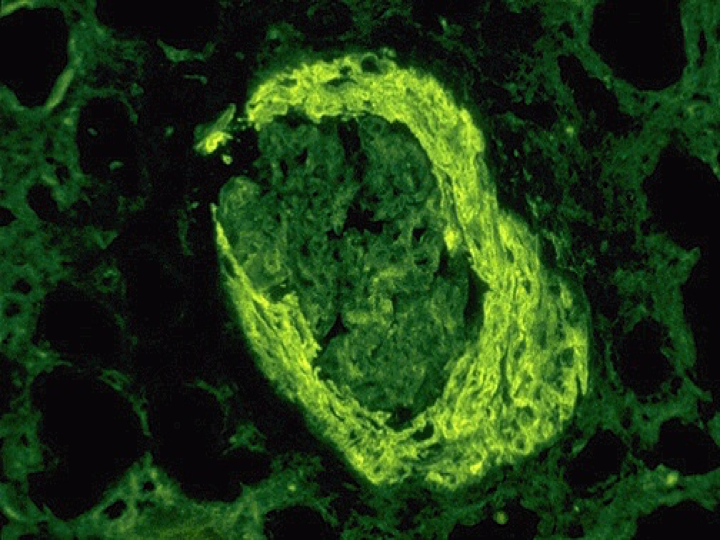

免疫荧光 Ⅰ型和Ⅳ型新月体性肾小球肾炎显示IgG和C3沿肾小球毛细血管壁呈线状沉积;Ⅱ型新月体性肾小球肾炎可见不同的免疫球蛋白和C3在肾小球不同部位沉积;Ⅲ型和Ⅴ型新月体性肾小球肾炎IgG和C3阴性。

电镜下:肾小球基底膜不规则增厚,有时可见基底膜断裂缺损,新月体形成。Ⅱ型新月体性肾小球肾炎可见电子致密物沉积。